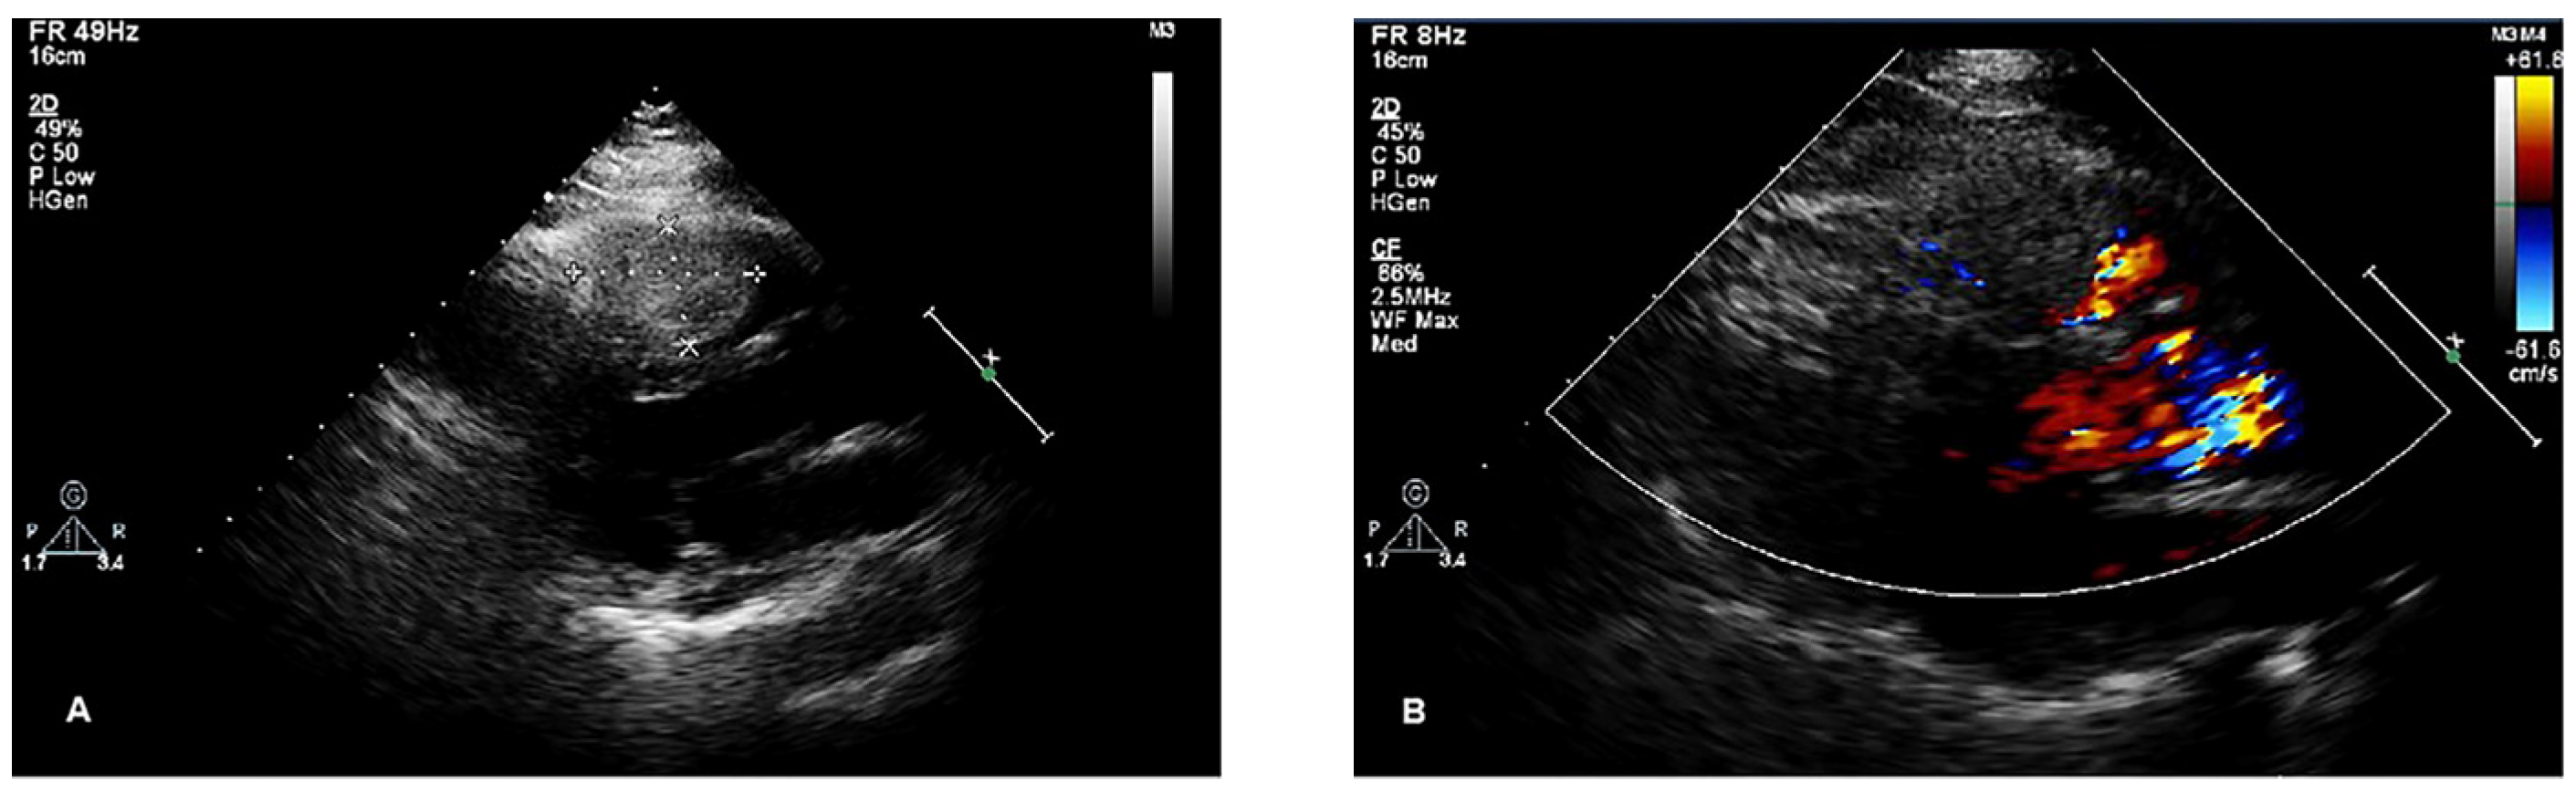

Cardiac non-contrast CT confirmed the presence of a round mass slightly high in density within the right ventricle, with a CT value of 70 Hounsfield Units (HU). In the contrast-enhanced scan, early, rapid, and homogeneous enhancement was noted, with a CT value of approximately 131 HU, and further enhancement with a CT value of approximately 213 HU, which was similar in density to the patient’s thyroid gland on non-contrast and contrast-enhanced CT (Figure 2). Coronary computed tomography angiography (CCTA) suggested that the mass was perfused by a branch arising from the left anterior descending artery (Figure 2).

Figure 2.

Cardiac CT imaging of the lesion. (A) The mass was slightly high in density on non-contrast CT scan. (B–E) The mass demonstrated obvious homogeneous enhancement on contrast-enhanced scan, which resembled the patient’s thyroid enhancement pattern. (F) CCTA images showed that the mass was perfused by a branch arising from the left anterior descending artery. White arrows indicate the location of the mass in each image.